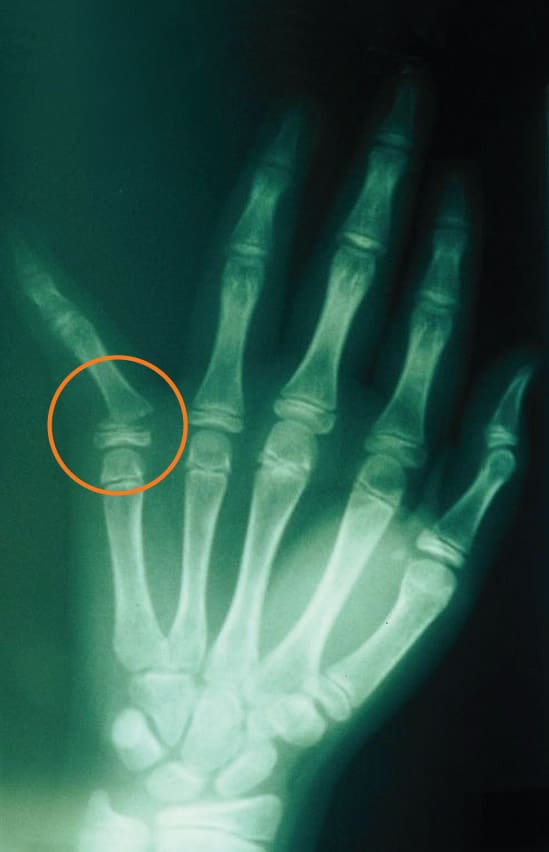

Fractures in children may be non-displaced, which means that it is a “hairline” fracture, or a fracture that has not broken into two separate pieces. Other fractures may be displaced, which means that it is a complete fracture that has broken into two or more pieces with some shift in position so that the ends of the broken bone are not in alignment (see Figure 1a). Fractures may occur in the shaft of the bone, or near the end, or in the joint.

Children are able to “remodel” (the specific process of bone resorption and formation) a broken bone after it heals and as the child grows. Certain breaks may not have to be re-aligned perfectly because of this ability to remodel with growth. Younger children have greater potential for remodeling with growth. Fractures with angulation in the same direction as joint motion (bending and straightening) also have greater potential to remodel. Fractures that disrupt the surface of a joint usually need to be realigned as precisely as possible, though, and may need surgery to do so (see Figure 2a). Fractures that are rotated or twisted, or angled out to the side also need to be realigned more precisely as they have less potential to remodel (see Figure 1a).